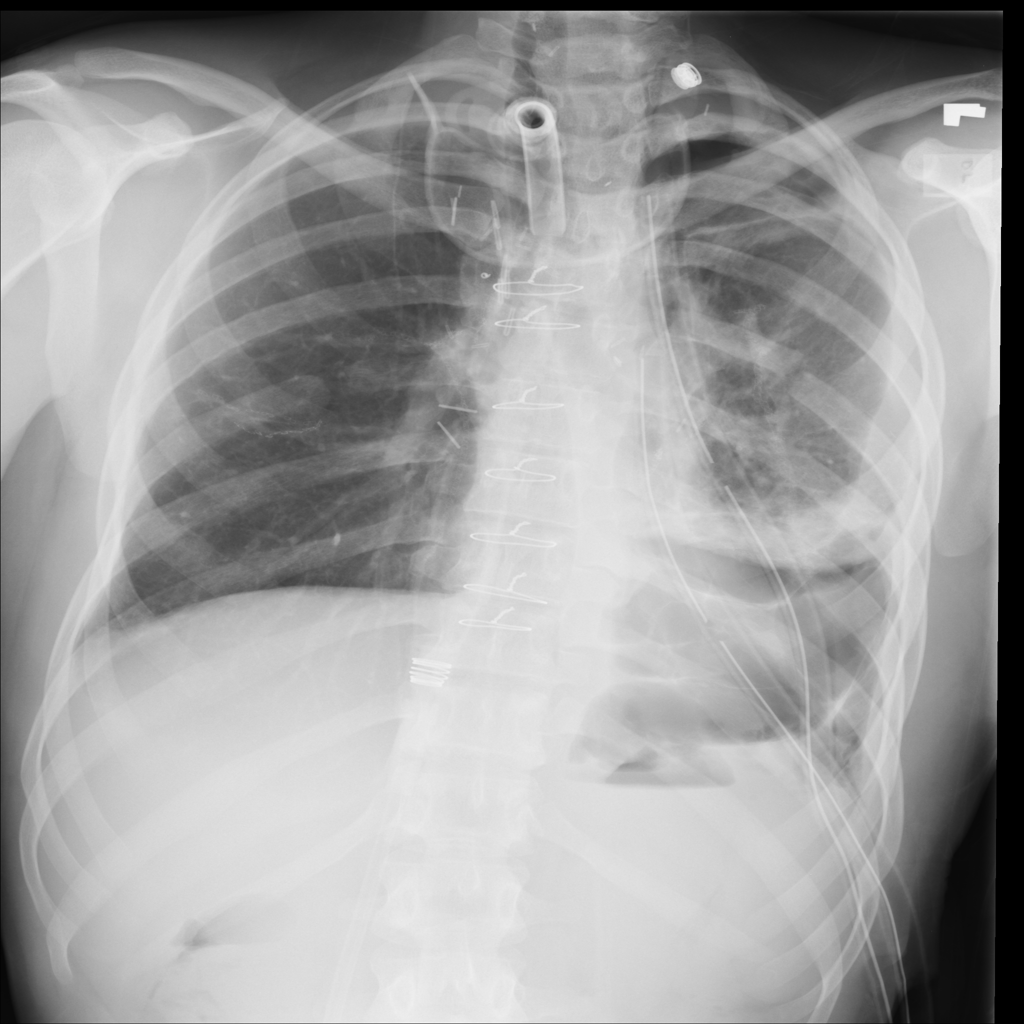

Showing up to 90 reference images for Pneumothorax.

PAT-4639 · IMG-013Pneumothorax

PAT-4639 · IMG-013

AP